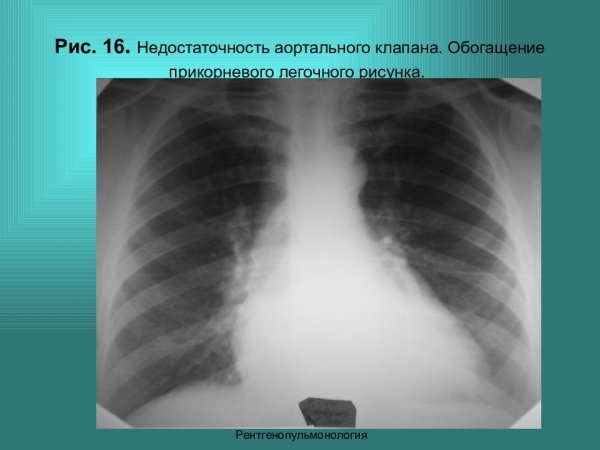

Недостаточность аортального клапана рентген